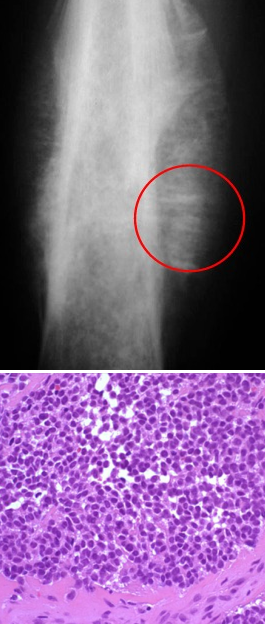

An 11 year old boy comes to see you complaining of pain in his middle thigh, fatigue and recurrent infection. Biopsy of the lesion and x-ray are shown below. What is the pathophysiology of his condition?

Note the “onion-skin” tumor and the small blue malignant cells. This is Ewing sarcoma. Tumor cells are generated from a translocation t;(11,22).